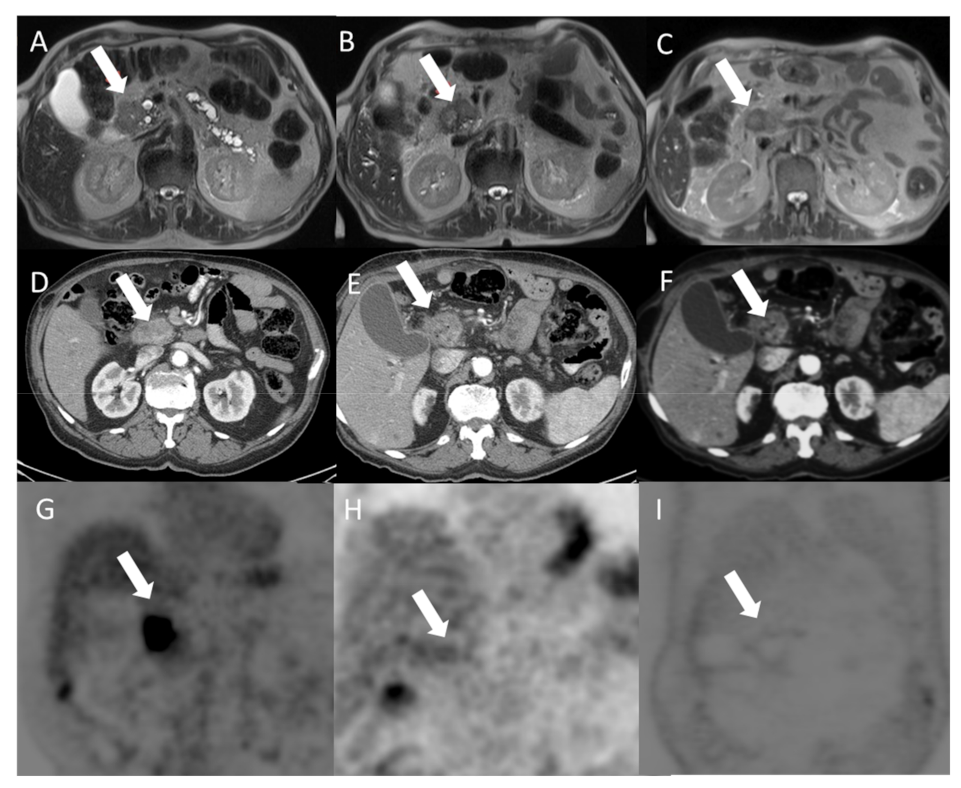

2.3.Imaging Techniques

3.1. Primary Endpoint Outcome (Local Disease Control and Overall Survival)

3.2. Secondary Endpoints Assessment (Feasibility and Safety)

- Granata, V.; Fusco, R.; Setola, S.V.; Piccirillo, M.; Leongito, M.; Palaia, R.; Granata, F.; Lastoria, S.; Izzo, F.; Petrillo, A. Early radiological assessment of locally advanced pancreatic cancer treated with electrochemotherapy. World J. Gastroenterol. 2017, 23, 4767–4778. [Google Scholar] [CrossRef] [PubMed]